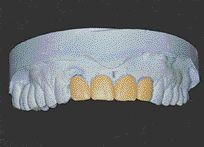

CROWNS MAKING A SEAL VS. CROWNS HELD BY RESIN? The jury is still out. Only the test of time will tell. Will new technology outperform the old standard? Are the oldies still the goodies? Today’s revolution in dental materials is driven by public demand. People want natural looking white teeth containing no metal. “Metal is … Read more